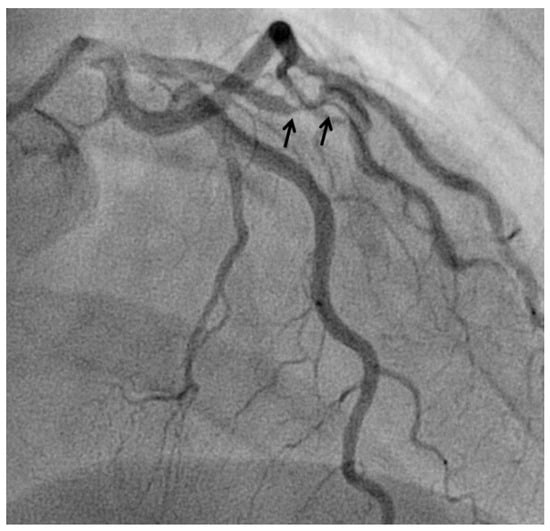

At angiography, coronary artery vasculitis may manifest under the form of coronary stenosis, aneurysm (Figure 2), dissection (Figure 3, most frequent in eosinophilic periarteritis), spasm (Figure 4), or coronary rupture (Table 1). Sudden death, typical angina, acute myocardial infarction, atrial and ventricular arrhythmias, conduction disturbances, or cardiac failure have all been described []. Although no specific finding at coronary angiography allows a safe diagnosis, features associated with early, advanced, or atypical coronary artery disease may suggest an inflammatory etiology. For example, Kawasaki disease and polyarteritis nodosa are often associated with large aneurysms []. Polyarteritis nodosa often features multifocal aneurysms with a “beads on a string” or nodular appearance [], which are also present in patients with anti-neutrophil cytoplasmic antibody (ANCA)-associated vasculitis and Behcet’s disease []. The arterial lesions in Behçet disease may be occlusive or aneurysmal []. Giant cell arteritis has been associated with long coronary lesions [], and in Takayasu’s arteritis, coronary lesions have been classified in three main types: 1, stenosis or occlusion of the coronary ostia (60–80%); 2, diffuse disease that may involve all epicardial branches or only focal segments (10–20%); and 3, coronary aneurysms (0–5%) [].

Figure 3.

Spontaneous dissection (arrows) in a 45-years old woman causing non-ST elevation myocardial infarction.